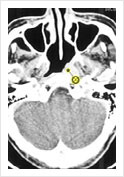

• Early NPC on Axial CT Scan